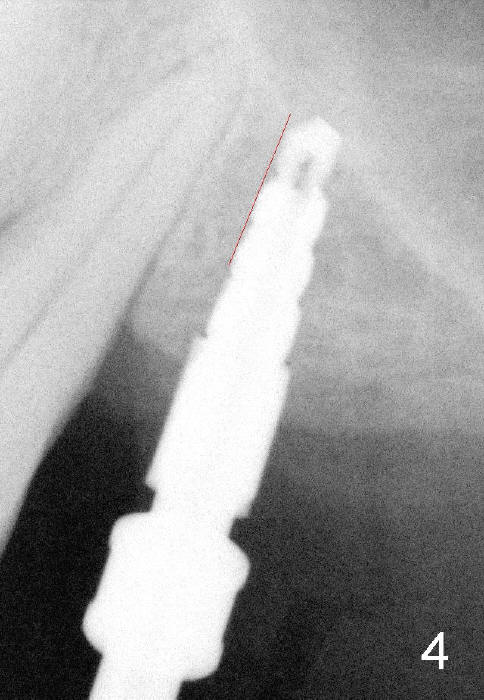

Fig.1: preop; Fig.4: 3.5x11 mm drill; Fig.5': 4.5x11 mm tap; Fig.6: 4.5x11 mm implant. Red line: original mesial apical outline of osteotomy. It shows that it is possible to change trajectory at late stage of osteotomy by changing angulation and position of burs, paying attention of orientation of tap and implant while inserting them.

Although there is no bone graft, implant placement apparently leads to sinus lift (Fig.6 arrowheads).